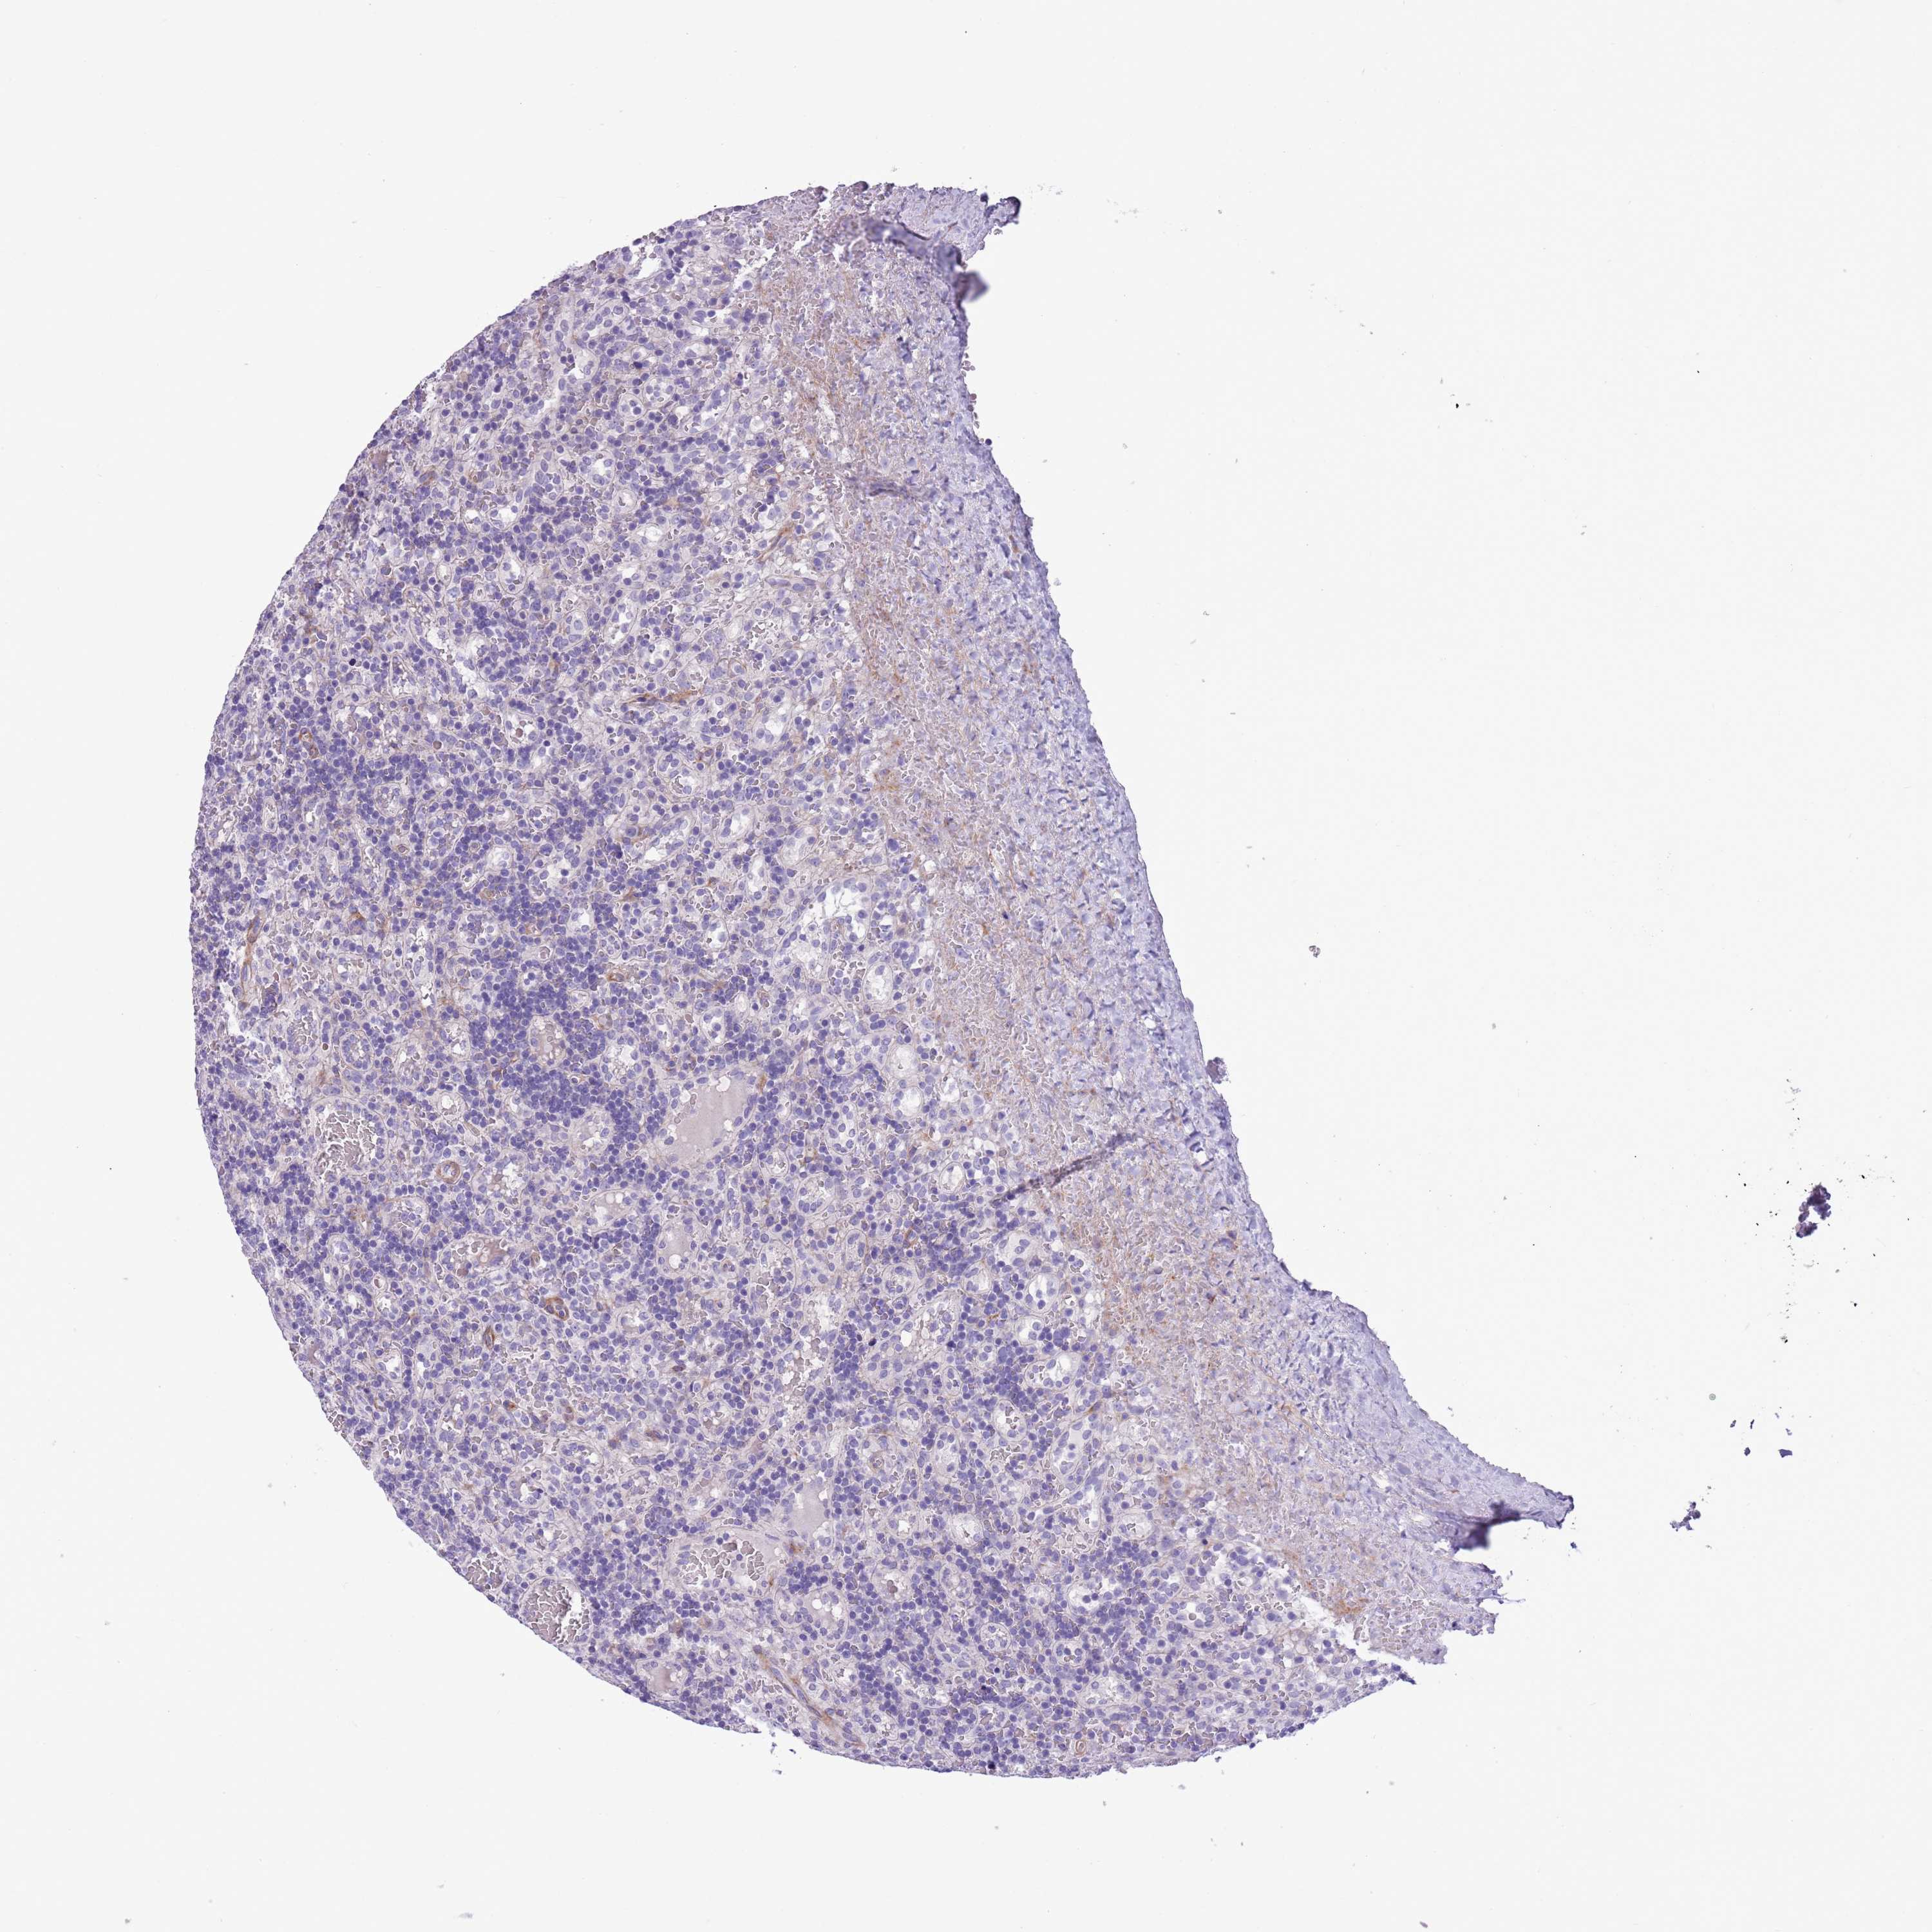

CANCER LYMPHOMA Show tissue menu

LYMPHOMA - Protein expressioni

A mouse-over function shows sample information and annotation data. Click on an image to view it in a full screen mode. Samples can be filtered based on level of antibody staining by selecting one or several of the following categories: high, medium, low and not detected. The assay and annotation is described here.

Antibody stainingi

Antibody staining in the annotated cell types in the current human tissue is reported as not detected, low, medium, or high, based on conventional immunohistochemistry profiling in selected tissues. This score is based on the combination of the staining intensity and fraction of stained cells.

Each image is clickable and will lead to virtual microscopy that enables deeper exploration of all samples and also displays staining intensity scores, fraction scores and subcellular localization as well as patient and tissue information for each sample.

Antibody HPA048965

Staining

High

Medium

Low

Not detected

Intensity

Strong

Moderate

Weak

Negative

Quantity

>75%

75%-25%

<25%

None

Location

Nuclear

Cytoplasmic/membranous

Cytoplasmic/membranous,nuclear

Hodgkin's disease, NOS

Malignant lymphoma, non-Hodgkin's type, High grade

Malignant lymphoma, non-Hodgkin's type, Low grade